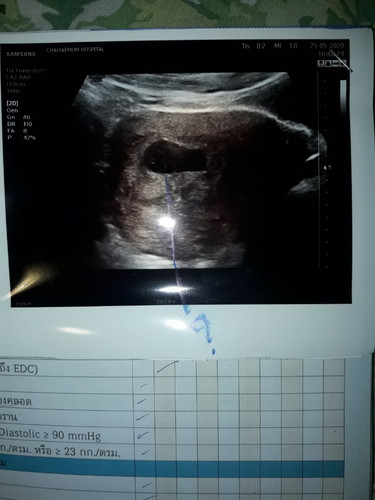

หมอบอกท้องลม!! 50/50

วันนี้ไปพบหมอมา 11w3d หมอเจอแต่ถุงครรภ์กับอะไรขาวๆน้อยๆอยู่ในถุง หมอเลยนัดอีก 1w ถ้าไม่เจอหมอบอกต้องยุติการตั้งครรภ์ ทำใจ ตั้งสติ ได้แต่ภาวนาขอให้เจอน้องนะ